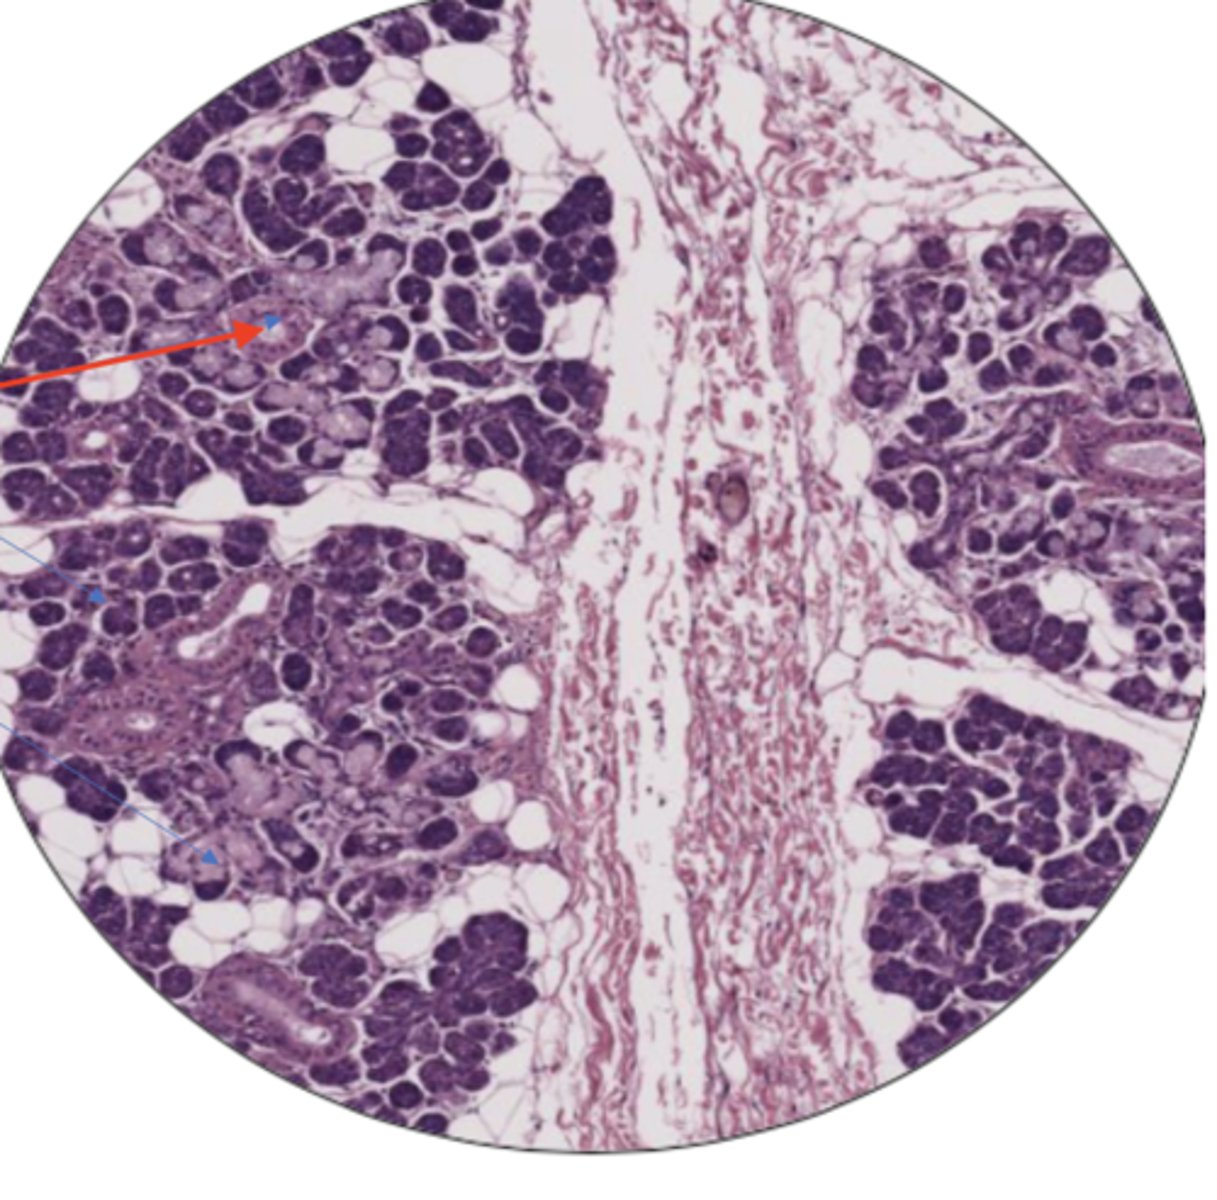

seminiferous tubule

leydig cells

sperm cell

sperm mass